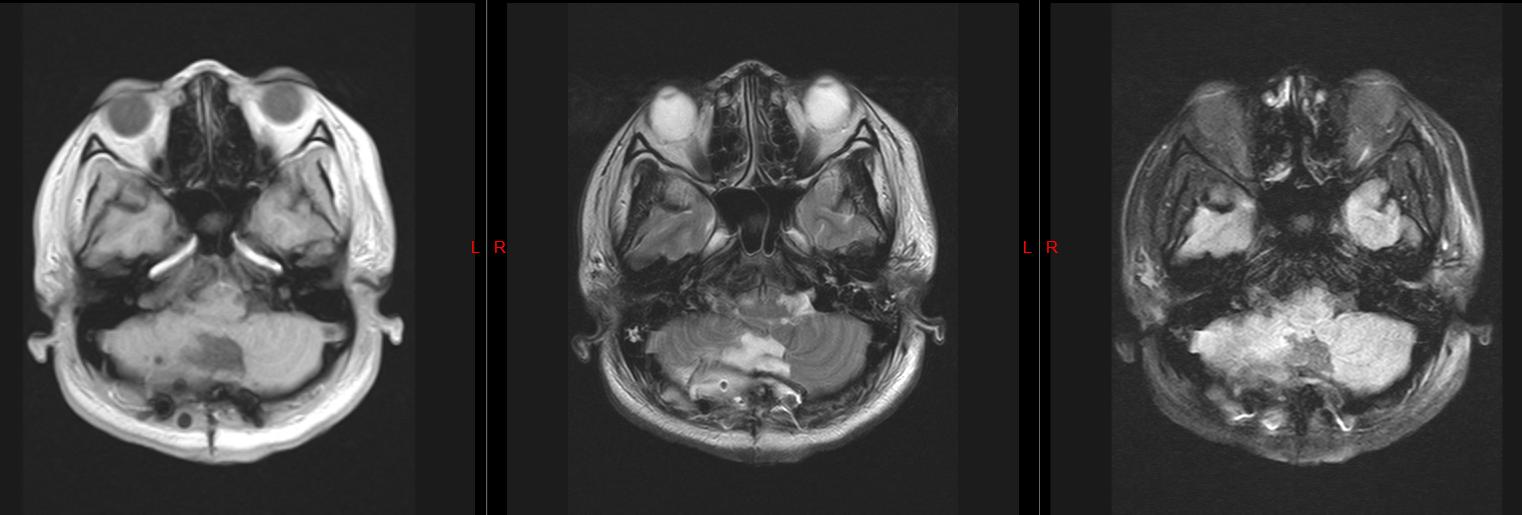

术中他们发现

我的小脑中长了“头发”

其实这些并不是真正意义上的头发,而是 原本应该分化成头发的细胞 ,在胚胎期发育异常,产生异位,跑到脑子里生根发芽。

皮样囊肿的基底层内含有较多的纤维组织及真皮层, 内含皮肤的附件如汗腺、皮脂腺及毛囊等 。

手术中张辉主任

将肿瘤组织及包膜完整切除

并且解决梗阻性脑积水的问题